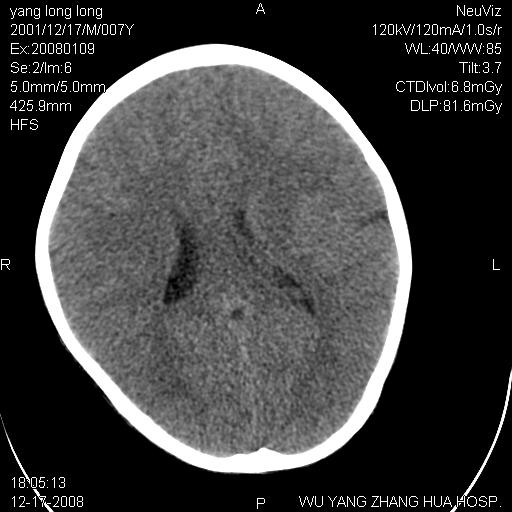

标题: PED1686:M7Y,头外伤,家人及自诉平时无任何不适。 [打印本页]

标题: PED1686:M7Y,头外伤,家人及自诉平时无任何不适。

考虑蛛网膜囊肿,请老师们看看多指导指导。

多考虑大枕大池。本例颅骨歪歪的,灶后枕骨似有膨胀征像(为蛛网膜囊肿征像),但整个左侧枕叶后方枕骨均有向后膨隆,所以暂不考虑蛛网膜囊肿。必要时随访

鉴别巨大枕大池与蛛网膜囊肿之间,倾向前者。

枕大池蛛网膜囊肿

蛛网膜囊肿可能性大

考虑枕大池蛛网膜囊肿。建议必要时mri检查。

病变向两侧延伸,颅骨内板受压侵蚀,似有张力!!还是考虑蛛网膜囊肿!!